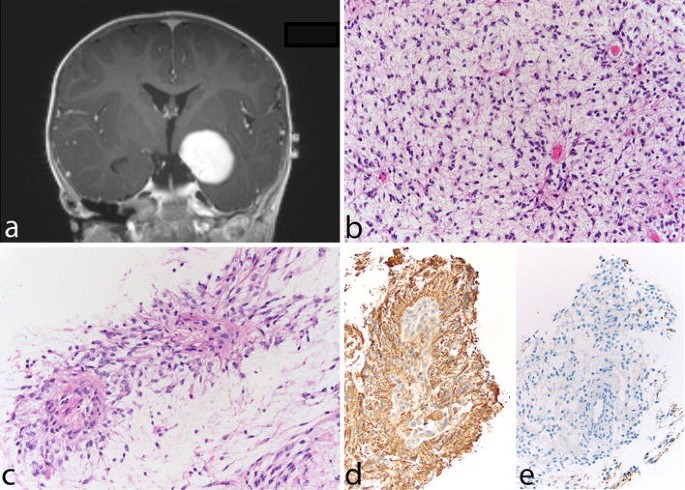

Микрофотографии гистологии глиобластомы головного мозга